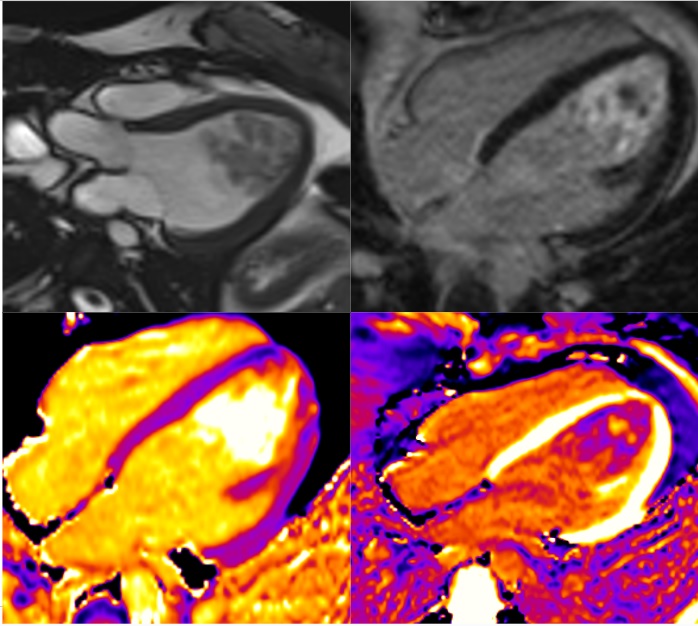

AMI inferolateral medial segment, embolic origin

Surgical specimen